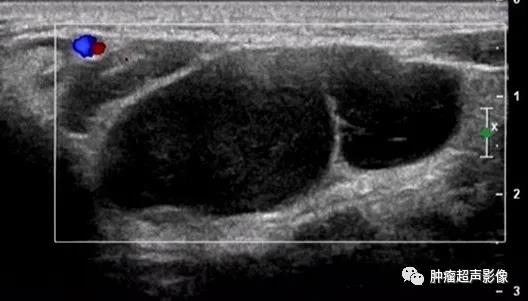

手术证实的口外型舌下腺囊肿:颌下腺周围不规则无回声向口底部延伸,边缘毛糙,无明确的包膜,透声佳,无血流。

手术证实的口外型舌下腺囊肿:颌下区不规则无回声向口底部延伸,下颌舌骨肌有缺损,边缘毛糙,无明确的包膜,透声佳,无血流(来自微信好友会诊病例)。

手术证实的口外型舌下腺囊肿:颌下形态欠规则无回声,大部分边缘光整,口底侧局部边缘毛糙、无明确的包膜,透声欠佳,无血流,比较容易误诊。